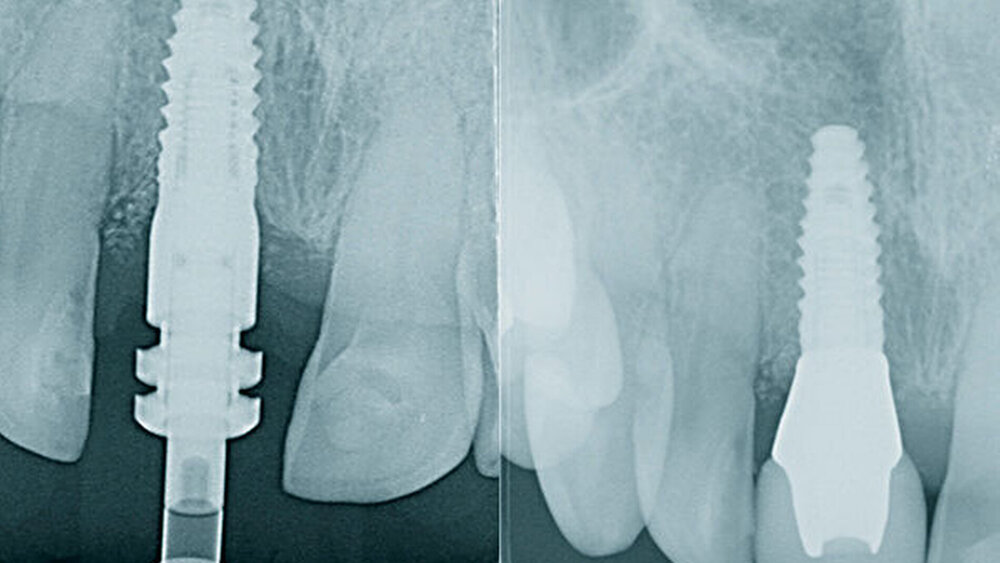

Seit rund einem halben Jahr testen Sie die neue PROGRESSIVE-LINE. Was sind die Hauptindikationen?Hermann:Im Juni 2018 haben wir in unserer Praxis in Zusammenarbeit mit der Abteilung R&D (Forschung & Entwicklung) von CAMLOG mit der klinischen Dokumentationsphase des CAMLOG PROGRESSIVE-LINE Implantats begonnen. Bis dato haben wir zirka 80 Implantate bei einer ausgewogenen Verteilung in Bezug auf verschiedene klinische Indikationen dokumentiert. Die Dokumentation des neuen Implantatsystems erfolgte im Hinblick auf die erzielte Primärstabilität in Abhängigkeit von der Knochenqualität (dies wurde mit der Chirurgieeinheit iCHIRO-PRO durchgeführt) und die Verlaufskontrolle der knöchernen Stabilität des Implantats mit dem Osstell-ISQ. Zudem wurde anhand eines Beobachtungs- und Dokumentationsbogens relevante Parameter während der Einheilungsphase erfasst. Momentan befindet sich die Hälfte der Implantate schon in der postprothetischen Dokumentationsphase. Unsere Erfahrungen in Bezug auf eine sicher zu erzielende Primärstabilität und eine zuverlässige Osseointegration sind durchweg positiv.

In welchen klinischen Anwendungen bietet das Implantat Vorteile?Hermann:Das neue CAMLOG PROGRESSIVE-LINE Implantat besticht durch sein innovatives parallel-konisches Makrodesign mit einem speziellen Gewinde, bei gleichzeitig bewährter Prothetikschnittstelle der Camlog-Linie. Dies bedeutet, dass in der chirurgischen Phase mit diesem Implantat eine zuverlässige Primärstabilität erzielt werden kann, speziell bei schwierigen anatomischen Voraussetzungen, wie z. B. bei der Sofortimplantation, bei reduzierter Kieferkammbreite oder konkav verlaufenden Alveoloarkämmen sowie bei weichem Knochen im Oberkiefer. Aufgrund des krestalen Verankerungsgewindes sehen wir zudem einen Vorteil bei der Platzierung des Implantats im Zusammenhang mit einer simultanen, offenen Sinusbodenelevation bei stark reduzierter Restknochenhöhe (2–3 mm). Auch einzeitige Verfahren lassen sich einfacher durchführen. Denn auch im kompromittierten Knochen erreicht das Implantat eine hohe vorhersagbare Primärstabilität.